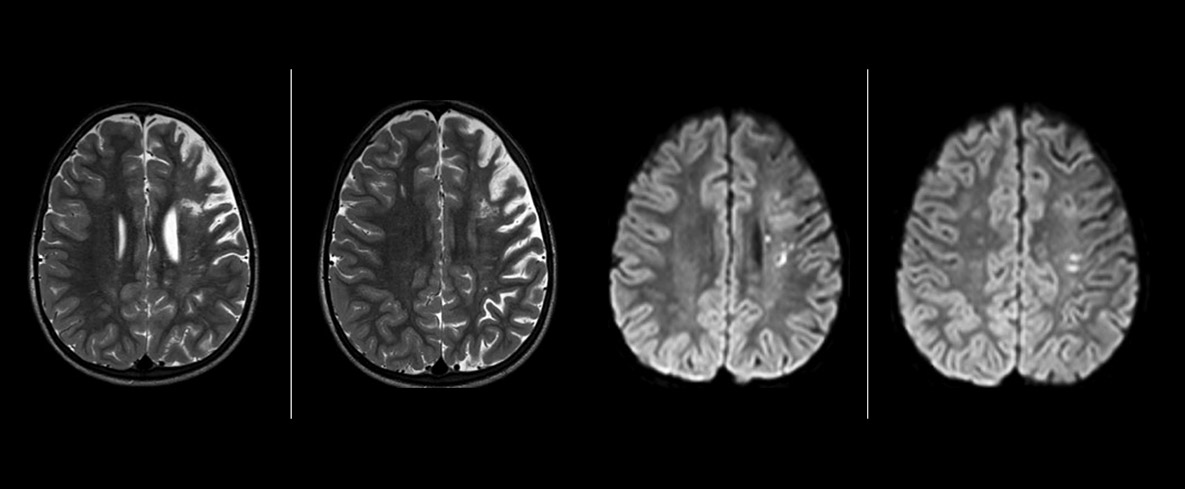

pCASL helps assess brain perfusion without contrast

Dr. Miller uses pCASL for all patients who present with chronic and acute cerebrovascular abnormalities such as acute stroke, as well as patients who present with signs of acute inflammation in the brain, and occasionally in patients with tumors, to assess the perfusion status of their tumor.

“In combination with diffusion weighted imaging, it can help give a more extended assessment of the degree of perfusion abnormality in a patient who is suffering acute ischemia. We have a number of patients who have chronic arterial insufficiency due to prior arterial abnormalities or acquired arterial abnormalities such as sickle cell disease or neurofibromatosis. Sometimes the child’s first manifestation of disease progression is a reduction in brain perfusion before stroke symptoms manifest clinically or in diffusion weighted imaging. We use pCASL to help delineate the perfusion abnormality.”

“We built up confidence in pCASL by comparing it to contrast-based perfusion imaging. Once we had confidence that it was representing what the contrast perfusions were representing, we increased our diagnostic confidence by serial imaging in either the acute stage or the long term stages in a number of patients with arterial abnormalities.

To other new users I would recommend to also start to interpret the pCASL images in comparison with other standard imaging – T2 and FLAIR and DWI – until the user gains confidence in interpreting these images by themselves.”